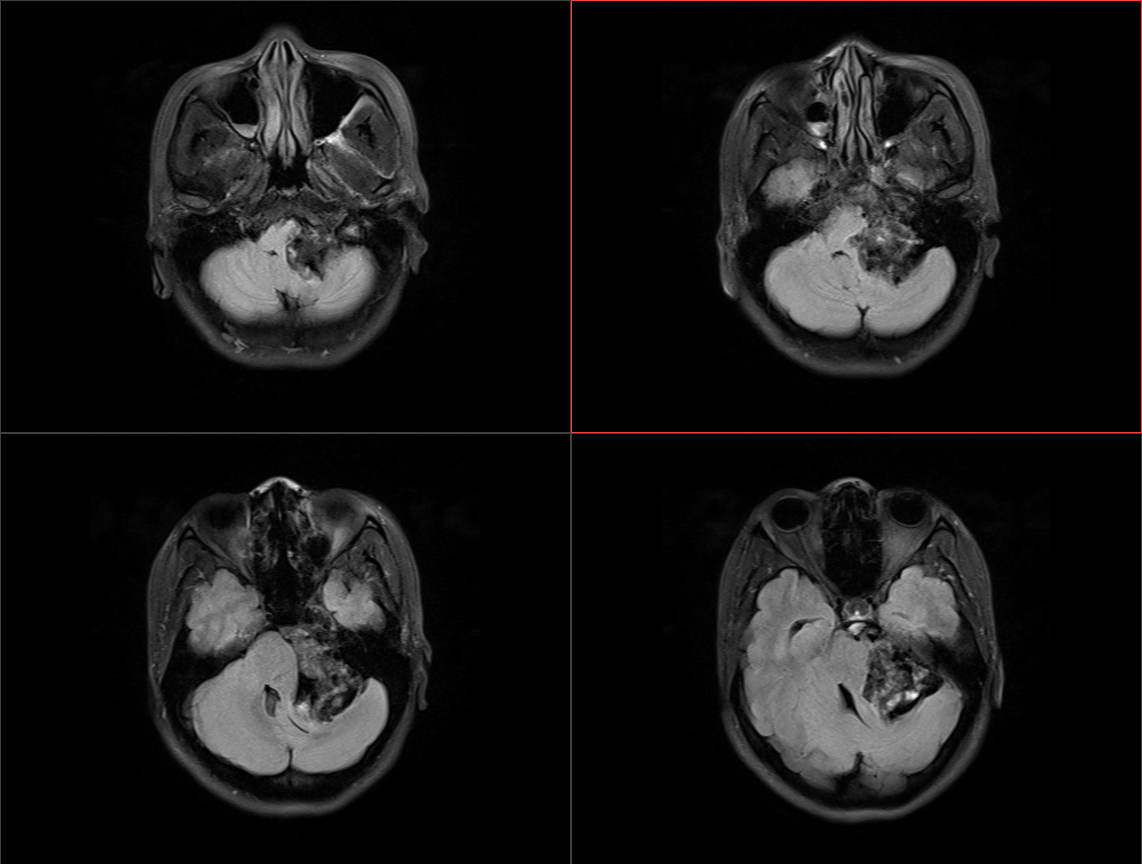

术后影像: